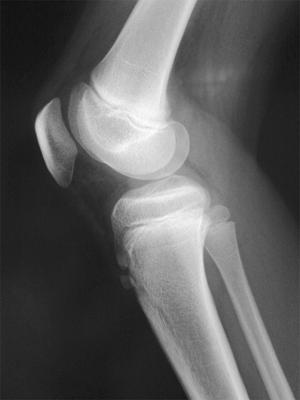

10歳の女児。1か月ほど前から運動後に膝の痛みを訴え、膝脛骨結節部に圧痛があった。単純エックス線写真を示す。最も考えられるのはどれか。

n6tHfVI9MddEkVgtif8GJ

1

腓骨骨折

2

膝靭帯損傷

3

膝半月板損傷

4

第1Köhler病

5

Osgood-Schlatter病

10歳の女児。1か月ほど前から運動後に膝の痛みを訴え、膝脛骨結節部に圧痛があった。単純エックス線写真を示す。運動後以外には膝の痛みの訴えはなかった。正しい対応はどれか。

jka6UPF5JytBzUX2dgxUT